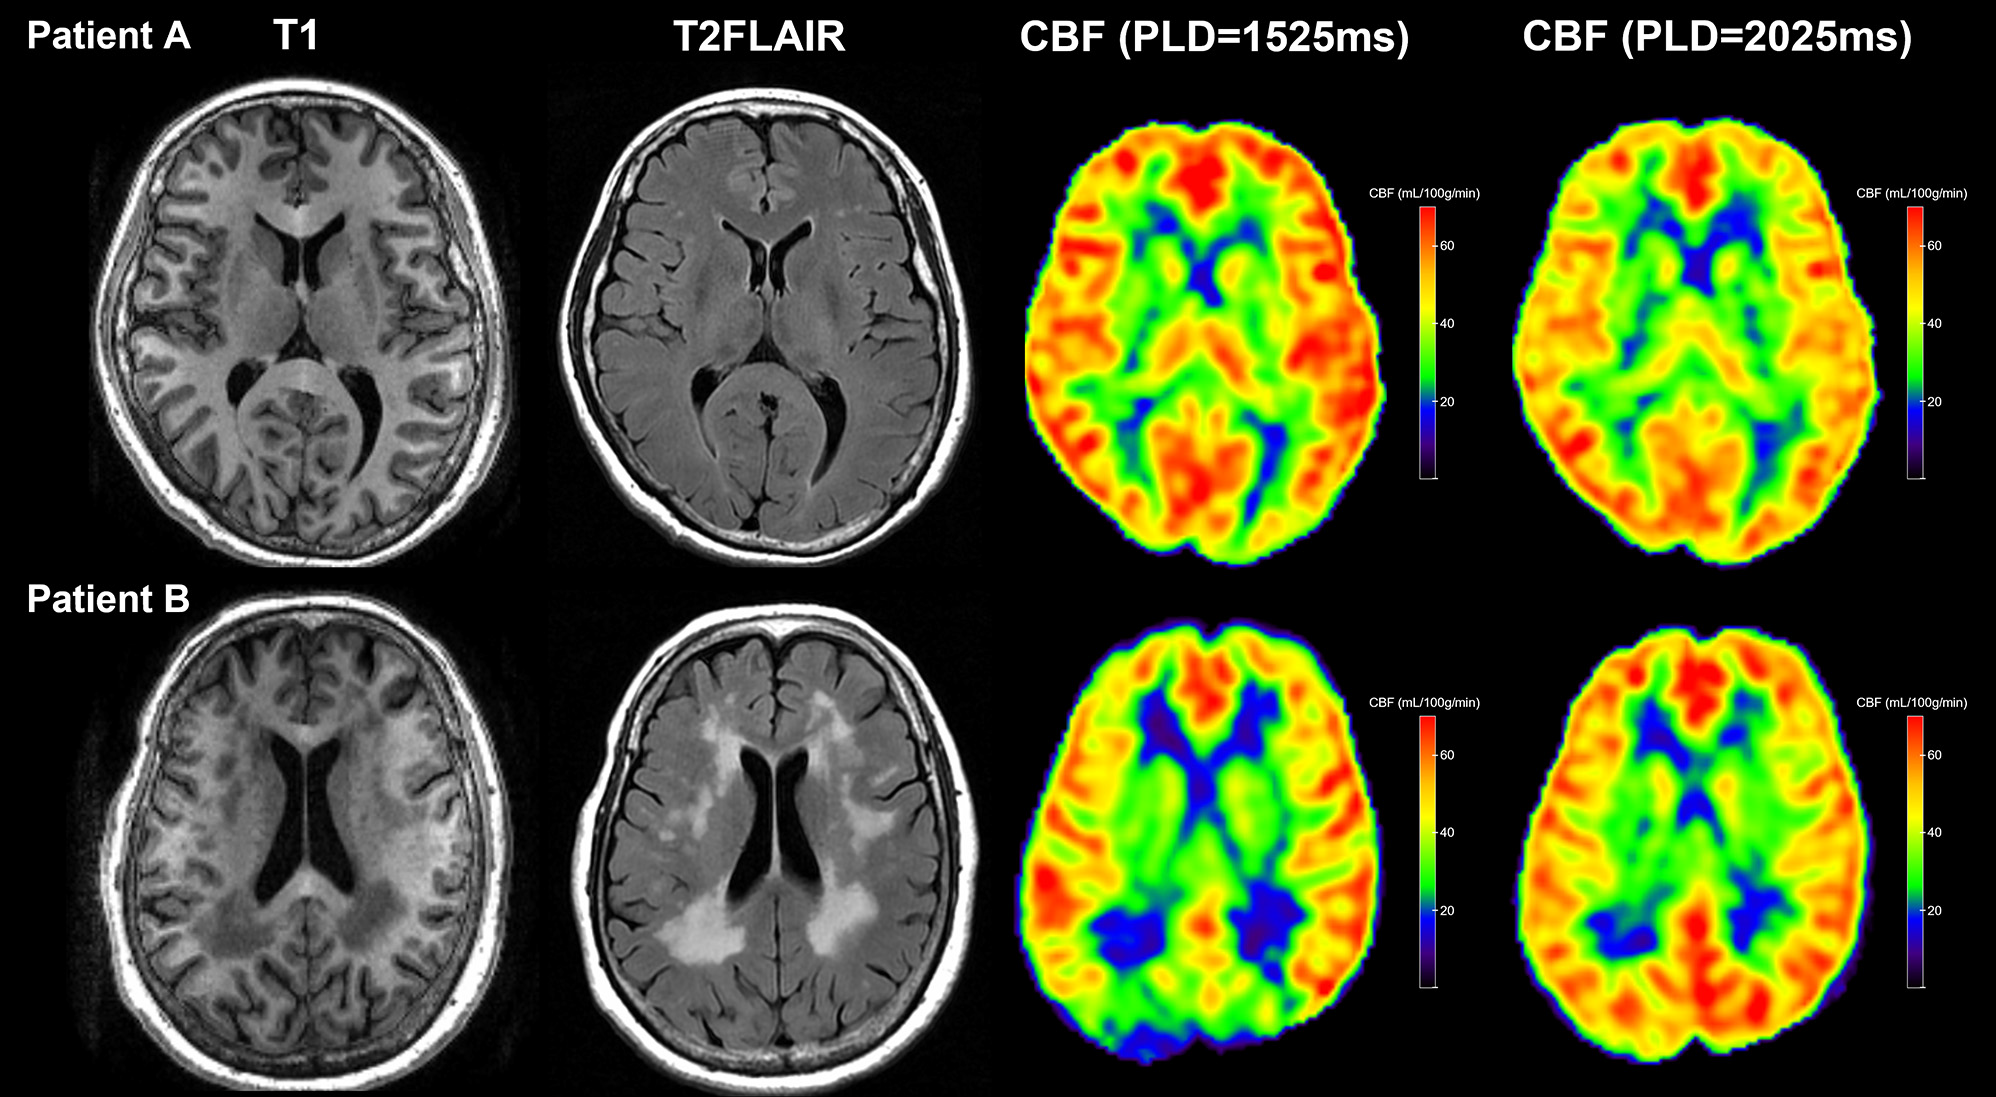

Due to the arterial arrival delay, here CBFPLD1.5 was significantly lower than CBFPLD2.0 in most subjects. We can also see that CBFPLD1.5 but not CBFPLD2.0 was associated with δCBF, confirming the influence of PLD on the measurement of CBF. Although this would be expected, because the real arterial arrival time still depended on each subject’s age and clinical status, the δCBF could reflect such differences. Indeed, some of our subjects had relatively young age and less vascular burden, so they had higher CBF when the PLD was short (Figure 2, upper row). On the contrary, those with large areas of WMH had significantly higher CBF when the PLD was long (Figure 2, lower row). Therefore, we believe larger δCBF was associated with longer arterial transit time.

Figure 2

Two representative patients with different WMH burdens. Upper row: Patient A had a low WMH burden and presented with higher global CBFPLD1.5 than CBFPLD2.0. Lower row: Patient B had a high WMH burden and presented with lower global CBFPLD1.5 than CBFPLD2.0.